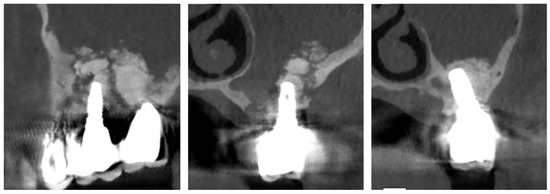

Figure 6. Maxillary sinus after gentle toilette without removing of Shneiderians’ membrane.

Figure 7. Buccal fat paddle isolation.

Figure 8. Buccal fat pad advancement.